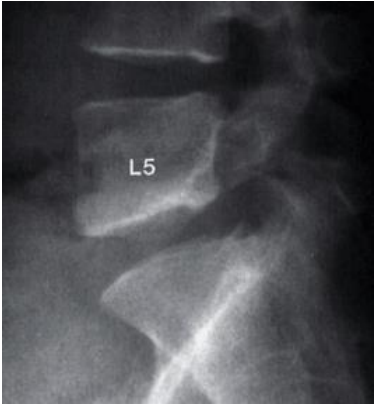

Observe a imagem abaixo, radiografia simples lateral aproximada da coluna lombar de um paciente de 40 anos de idade que se apresenta com dor lombar.

Diante do exposto, é correto afirmar que